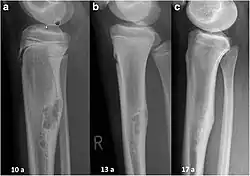

Non-ossifying fibroma of tibia

The most common bone tumor is a non-ossifying fibroma.[4] Average five-year survival in the United States after being diagnosed with bone and joint cancer is 67%.[5] The earliest known bone tumor was an osteosarcoma in a foot bone discovered in South Africa, between 1.6 and 1.8 million years ago.[6]